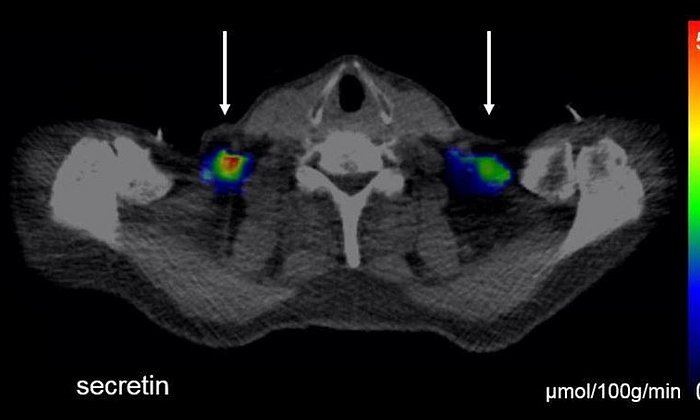

Gemeinsam mit ihren Teams an der TUM und bei Helmholtz Munich untersucht die Wissenschaftlerin, wie Nervenzellen im Gehirn funktionieren und wie sie den Stoffwechsel im Zusammenspiel mit der Ernährung beeinflussen. Ein Schwerpunkt liegt dabei auf flüchtigen Substanzen – etwa Duftstoffe, die über die Nase eingeatmet werden und das Hunger- und Sättigungsgefühl im Gehirn beeinflussen können. Ziel ist es,  Duftmoleküle mit stoffwechselmodulierender Wirkung zu identifizieren und diese gezielt weiterzuentwickeln.